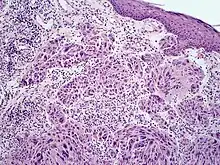

Melanoma with features of a Spitz nevus

Melanoma with features of a Spitz nevus (also known as a "Spitzoid melanoma") is a cutaneous condition characterized histologically with tissue similar to a spitz nevus and with overall symmetry and a dermal nodule of epithelioid melanocytes that do not mature with progressively deeper dermal extension.[1]